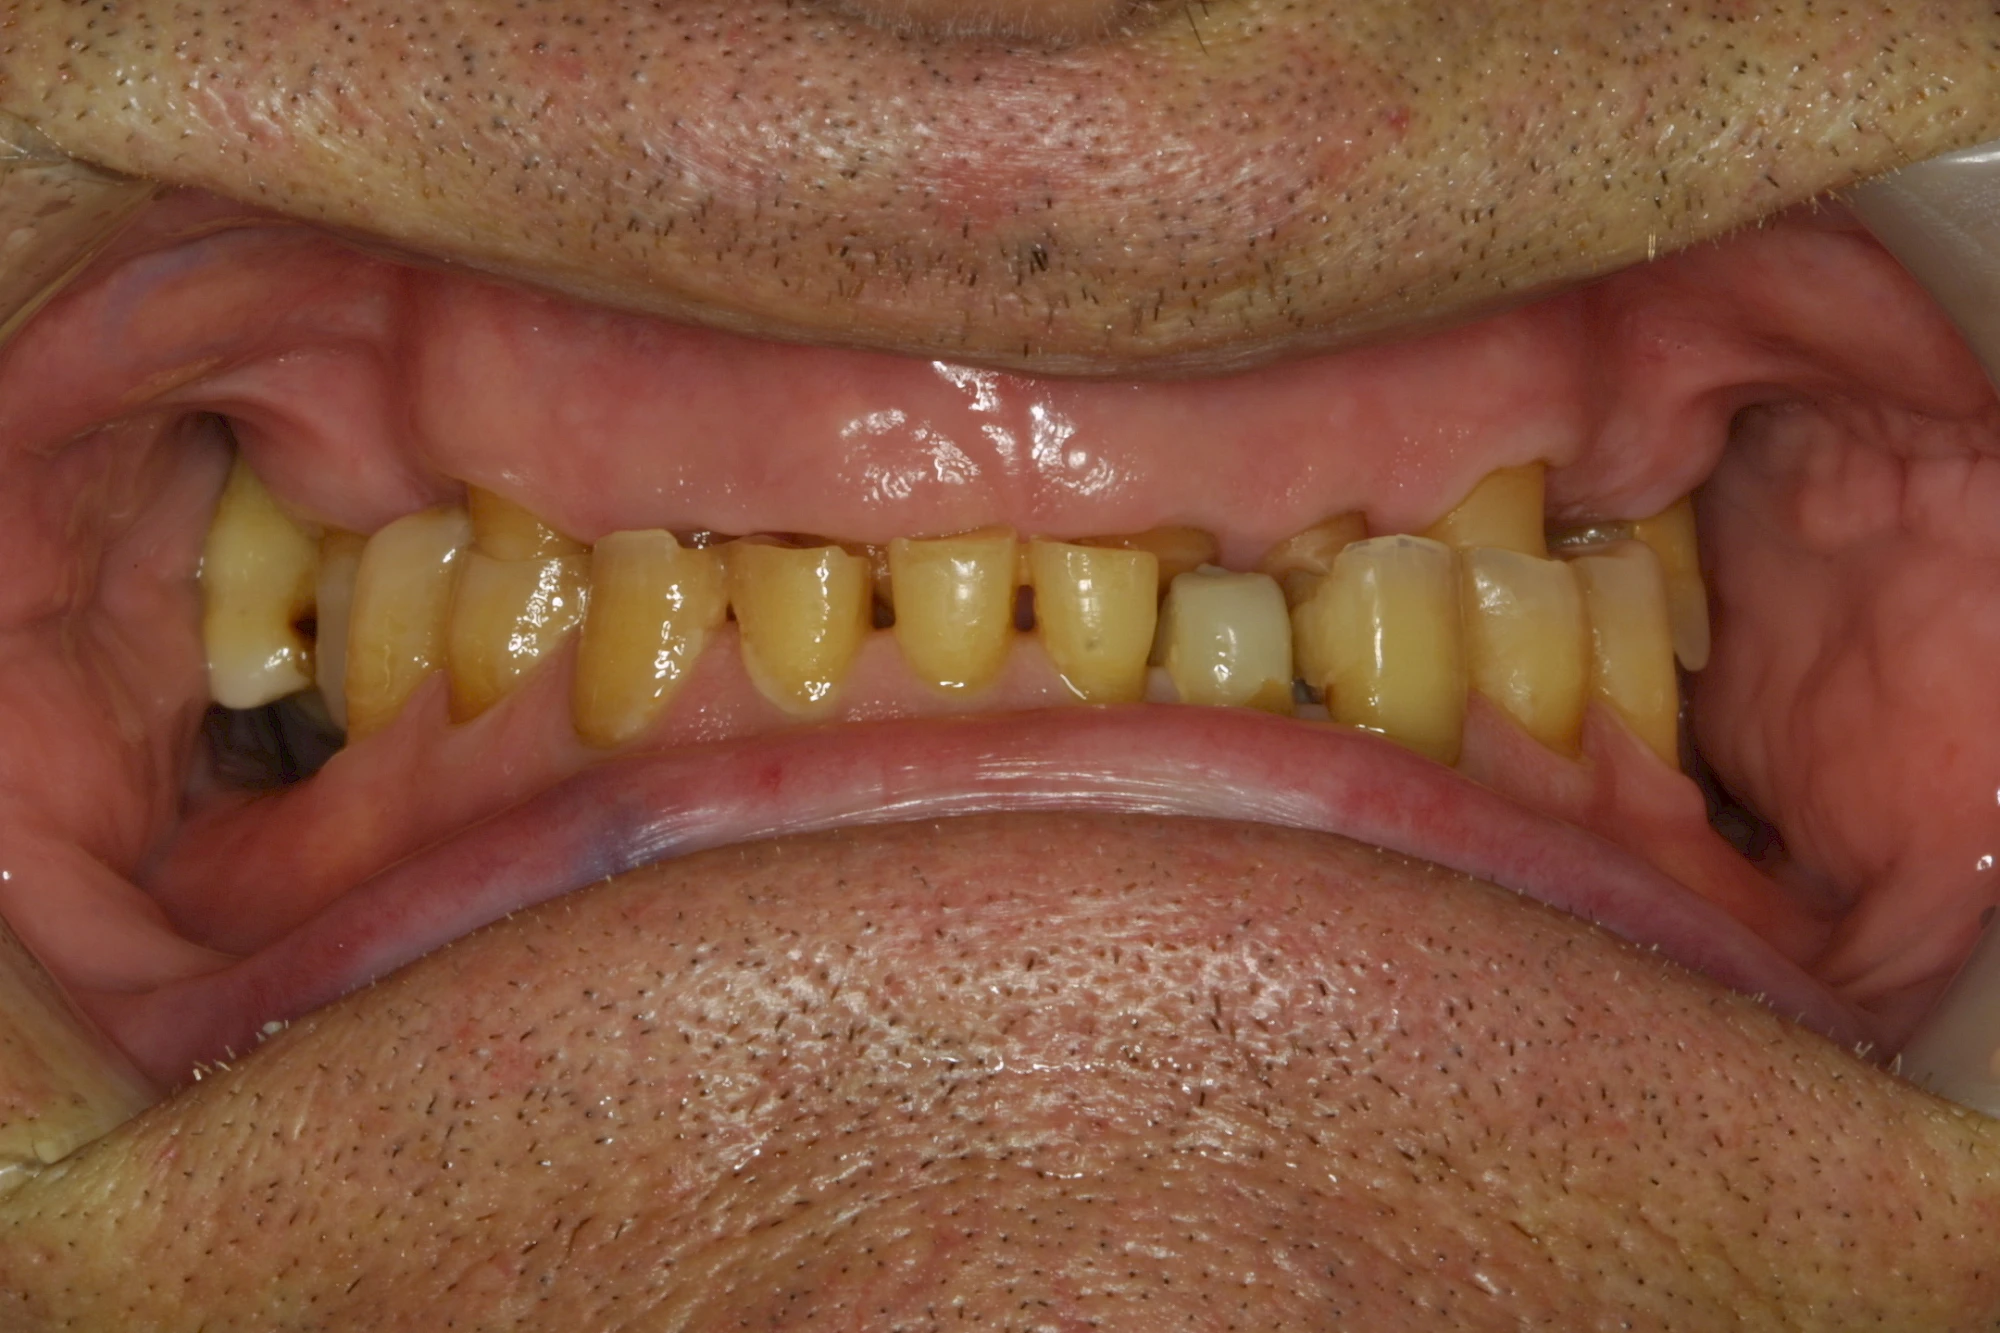

Keilförmiger Defekt

Eine Sonderform sind sogenannte keilförmige Defekte im Bereich der Zahnhälse. Hier geht man davon aus, dass Knirschen und Pressen in Kombination mit falschen Putzgewohnheiten (zu hoher Putzdruck, Verwendung von Zahnpasta mit hohen Abrasionswerten) eine Rolle spielen.